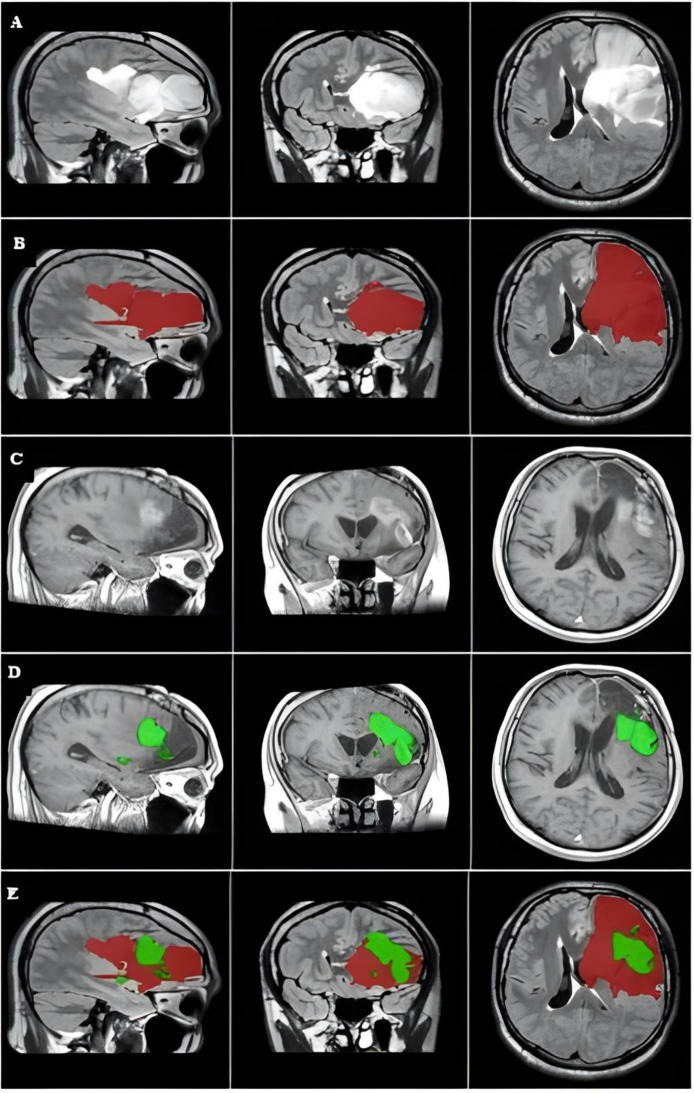

校正:术前用于鉴别胶质母细胞瘤边界的FLAIR图像。

Correction: Preoperative FLAIR images for identifying glioblastoma boundaries.